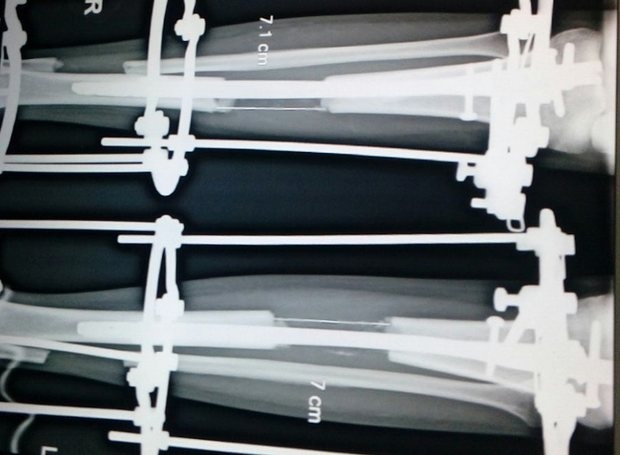

![]() |

| Ảnh chụp X-quang về quá trình phẫu thuật tăng chiều cao. Ảnh: Guardian |